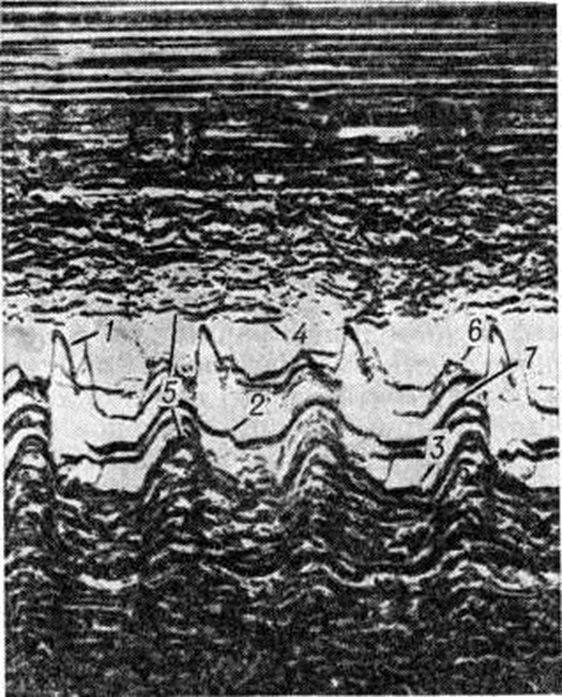

При эхокардиографическом исследовании выявляются признаки диффузного поражения миокарда: резкая дилатация желудочков, снижение сократительной функции миокарда. Определённые изменения происходят и при регистрации эхокардиограммы митрального клапана; обе створки клапана хорошо видны, располагаются в противофазе (так называемый рыбий зев), нередко выявляется сужение раннего диастолического и пресистолического пиков митрального клапана и формирование ступеньки в среднем и верхнем отделах нисходящего отрезка пресистолического пика (рисунок 8). Для застойной Кардиомиопатии характерна резкая дилатация камер сердца, преобладающая над гипертрофией, увеличение конечных систолического и диастолического размеров, снижение ряда показателей гемодинамики, в первую очередь ударного объёма. При сравнении степени и скорости укорочения циркулярных волокон миокарда выявляется значительное снижение первого и увеличение второго показателя.